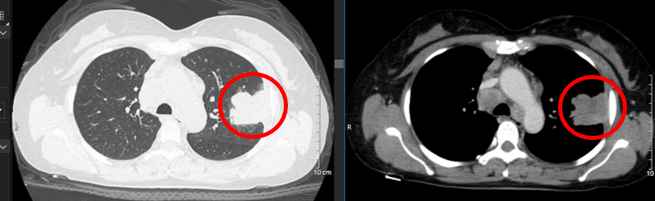

Chụp cắt lớp vi tính ngực: Hình ảnh u thùy trên phổi trái, kích thước 63x 84mm, sau tiêm ngấm thuốc không đồng nhất, tổn thương xâm lấn vào khí quản cắt cụt một vài nhánh phế quản, xâm lấn màng phổi. Hạch trung thất kích thước 34x39mm

Hình 3: Hình ảnh chụp cắt lớp vi tính ngực sau điều trị hóa chất 3 chu kỳ: U thùy trên phổi trái tăng kích thước so với trước điều trị, xâm lấn màng phổi (vòng tròn màu cam).

Như vậy:  Ở bệnh nhân này, sau điều trị hóa chất phác đồ AI x 03 chu kỳ, xuất hiện tình trạng bệnh tiến triển, thể hiện ở lâm sàng bệnh nhân xuất hiện thêm các triệu chứng (khó thở khi gắng sức, hạch cổ phải tăng kích thước); trên phim chụp cắt lớp vi tính ngực thấy khối u tăng kích thước (từ 48x46mm -> 63x 84mm), xâm lấn vào khí quản, màng phổi, hạch trung thất tăng kích thước (từ 25x16mm -> 34x39mm). Bệnh nhân này đã được hội chẩn hội đồng chuyên môn có chỉ định xạ trị triệu chứng u phổi kết hợp điều trị liệu pháp toàn thân.